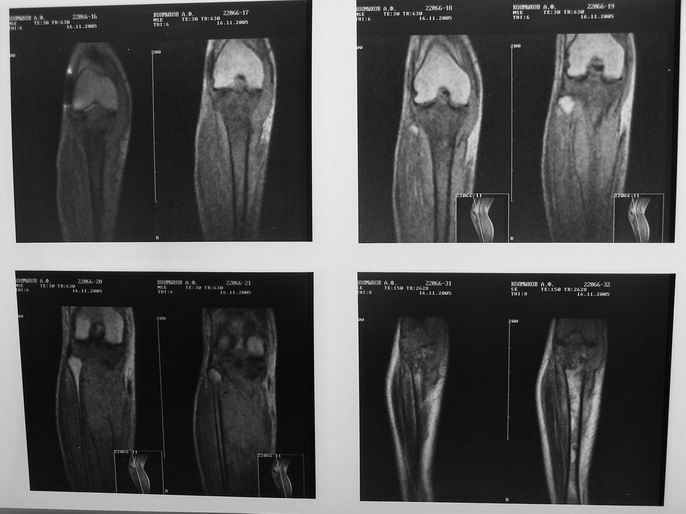

Ещё одно клиническое наблюдение - лимфома кости, до и после ПХТ и лучевой терапии.

Примите мои извенения, если я Вас чем-либо обидел. Никакого пренебрежения, просто хотел поделиться наблюдением, а главное, результатом консервативного (ПХТ и лучевая терапия) лечения.